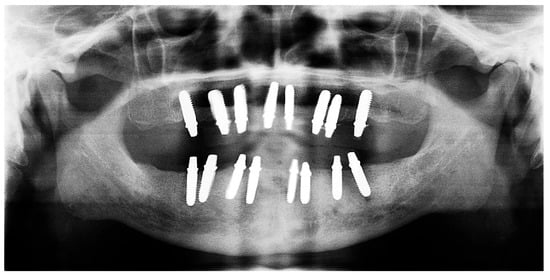

2.6. Sixth Visit

During the three-year follow-up period from October 2022 through September 2025, the patient was regularly recalled for evaluation. The peri-implant soft tissues remained healthy throughout the observation period. The gingiva surrounding the implants was consistently pink, firm, and showed no bleeding or suppuration upon probing of the peri-implant sulcus. At the last visit, probing depths ranged from 2–4 mm (mean 3 mm) in the maxillary arch and 1–3 mm (mean 2 mm) in the mandibular arch. No clinical signs of inflammation, edema, or granulation tissue were observed, indicating stable peri-implant mucosa and sustained biocompatibility of the materials used. Radiographic assessment revealed no crestal bone loss, and the prosthetic components remained functionally and esthetically intact, with no evidence of wear, fracture, or loosening. The patient reported high satisfaction regarding comfort, function, and appearance, further supporting the clinical success and reliability of this treatment approach (Figure 16 and Figure 17).

Figure 17. Panoramic X-ray at follow-up visit (taken 9 September 2025).